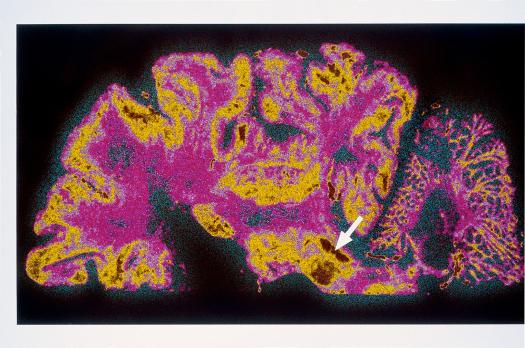

Deze nascholing biedt u een grondig overzicht van de ziekte van Parkinson en de farmacotherapeutische behandeling ervan. Aan de hand van recente cijfers, waaronder de schatting uit de ERGO-studie dat circa 61.000 mensen in Nederland aan de ziekte lijden, wordt duidelijk dat elke huisarts en apotheker te maken krijgt met (nog niet) gediagnosticeerde parkinsonpatiënten. De ziekte kent een progressief beloop en stelt hoge eisen aan het medicatiebeleid, dat veelal door de specialist wordt vormgegeven.

In deze nascholing staat de antiparkinsonmedicatie centraal. U leert over het beloop van de ziekte, de rationale achter verschillende medicatiestrategieën en de uitdagingen bij voortschrijdende symptomen. Er wordt ingegaan op de rol van levodopa, het nut van vertraagde afgiftepreparaten en het effect van combinatietherapieën. Ook is er aandacht voor de multifactoriële symptomatologie, waaronder cognitieve en psychiatrische complicaties zoals depressie en dementie.